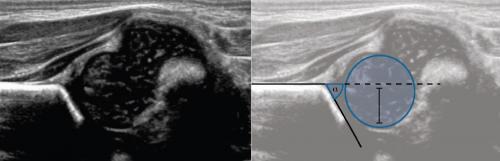

На первом этапе тазобедренный сустав сканируют в продольной плоскости. Проводят основные линии, измеряют костное покрытие головки, расстояние от лобковой кости до головки, ∠α и ∠β, а также определяют тип строения по Графу.

На втором этапе оценивают стабильность тазобедренного сустава сустава при пробе Барлоу-Ортолани. В нестабильном суставе костное покрытие головки уменьшается, а расстояние от лобковой кости до головки и ∠β увеличиваются.

Пока головка бедренной кости хрящевой плотности, имеется акустическое окно для исследования вертлужной впадины. При продольном сканировании документируют по два снимка: первый — обзорный, второй — с линиями и углами.

Проведите базовую линию по наружному контуру подвздошной кости и обозначьте головку бедренной кости, аппарат автоматически вычисляет степень костного покрытия головки. Костное покрытие головки в случаях предвывиха 40-50%, подвывиха

Когда головка смещается кнаружи, освободившееся пространство заполняет гиперэхогенная круглая связка и жир. При подвывихе и вывихе расстояние от лобковой кости до головки >6 мм, разница между бедрами >1,5 мм (3). Толстый хрящ лобковой кости считают вариантом нормы (4).